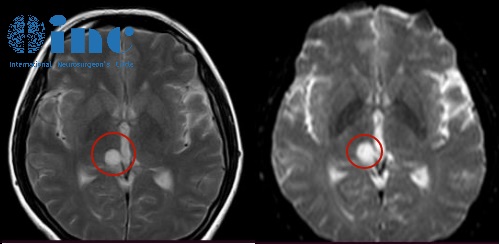

在丈夫的陪同下,我們來到當(dāng)?shù)伢w檢機(jī)構(gòu)進(jìn)行全身體檢,都顯示正常除了腦部CT片子,頭部核磁發(fā)現(xiàn)右側(cè)丘腦陰影,直徑約12mm??粗由先缁ㄉ状笮〉年幱?,我們慌了,的罪魁禍?zhǔn)自瓉砭褪撬?,然而這個(gè)陰影究竟是什么腫瘤?它會(huì)對(duì)我的身體繼續(xù)造成多大的損害?要怎么治療這個(gè)腫瘤?

為了盡快搞清楚這個(gè)病變是怎么回事,我們趕忙來到當(dāng)?shù)蒯t(yī)院再次檢查確認(rèn),醫(yī)院增強(qiáng)核磁共振診斷提示:右側(cè)丘腦異常信號(hào),建議到上一級(jí)醫(yī)院咨詢治療建議。

高難度丘腦膠質(zhì)瘤術(shù)后患者自述——影像圖

巴教授:“可以進(jìn)行手術(shù),但是目前由于陳女士的病變已經(jīng)存在了幾年并且癥狀較輕所以并不需要緊急手術(shù),建議進(jìn)行擇期手術(shù),目的是完全切除病變。腫瘤隨著時(shí)間的推移有可能發(fā)生惡變。為了不給腫瘤任何轉(zhuǎn)化為惡性膠質(zhì)瘤的機(jī)會(huì),較好是盡早通過手術(shù)切除,陳女士的核磁影像中,在T1-W序列中,腫瘤內(nèi)已經(jīng)有很小的強(qiáng)化,這可能是一個(gè)所謂的惡性轉(zhuǎn)化的熱點(diǎn);所以手術(shù)有必要。”